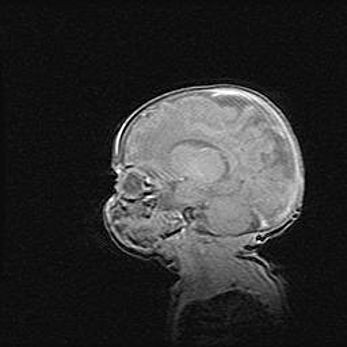

Множественные кисты обоих полушарий головного мозга, наибольшая из них в правой затылочной области. Ассиметричная атрофическая гидроцефалия.

Возраст: 7 месяцев

Вес: 5660 г

Пол: мужской

Окружность головы: 41,5 см

Срок гестации: 28-29 недель

Кисты головного мозга развиваются в результате многоочаговых некрозов вещества мозга и возникают вследствие перенесенной перинатальной инфекции, менингитов, энцефалитов, асфиксии, родовой травмы, расстройств мозгового кровообращения различного генеза. Образованию кист в веществе головного мозга плодов и новорожденных способствуют такие факторы, как высокое содержание в нем воды, недостаточная (или отсутствие) миелинизация и слабая астроглиальная реакция на повреждение.

Кисты могут сочетаться с гидроцефалией и другими поражениями головного мозга.